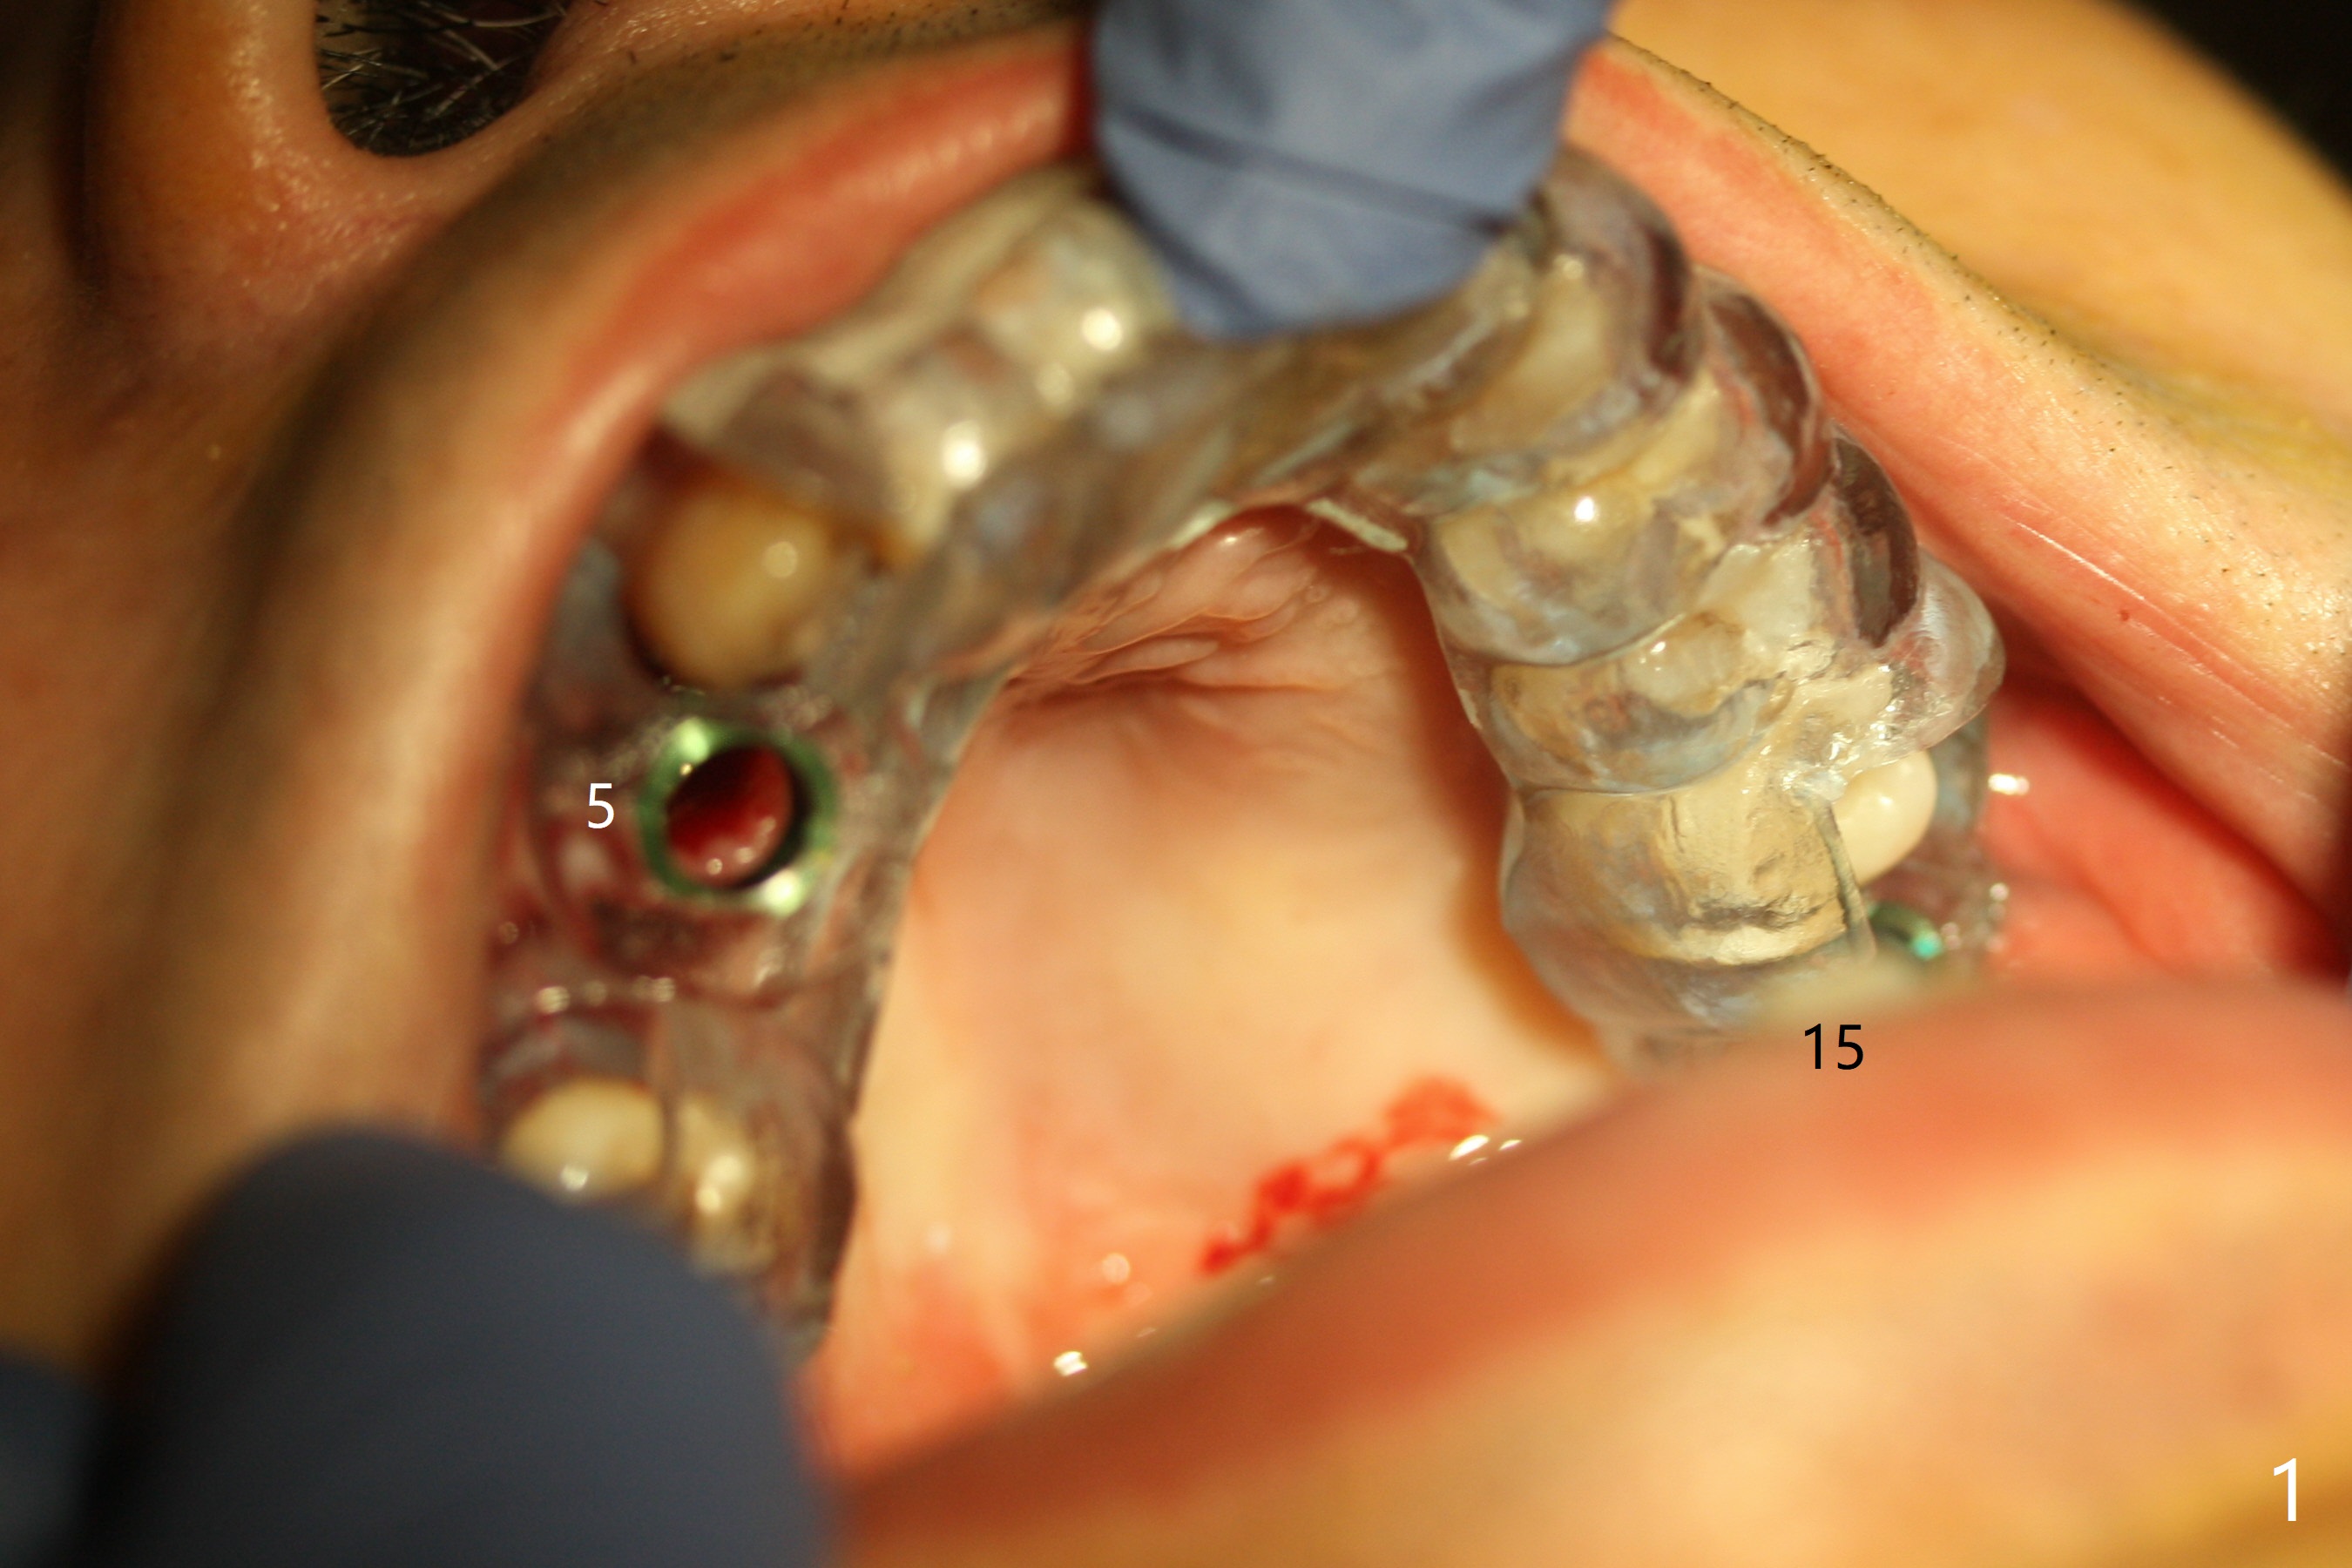

Today schedule is to extract the teeth #4 and 5 and place an implant at #5. When the latter is done, it appears that the implant at #15 should be placed at the same appointment (Fig.1). Once an abutment is placed at #5 (Fig.2 A, 5) for temporary crown (Fig.4 T) , the guide may be not seated again unless the crown is removed. Luckily the implant placement at #15 is quick and smooth with the guide (Fig.3,6). The implants seem to be covered by the bone 4 months postop (Fig.7,8). #15 abutment screw needs retightening because of long crown 1.5 months post cementation. Access hole is palatal. There is premature contact in lateral movement. The buccolingual occlusal table is large at #14 and 15. In fact there is more occlusal contact at #14 than #15 in centric occlusion. Tissue level implants should have been placed to reduce implant/abutment loosening. The incomplete abutment seating (Fig.5,7) is noted after retightening the loose cantilever FPD 1 year post cementation (Fig.9 <). After removal of the FPD, the abutment is reseated completely without interference of the proximal contacts (Fig.10).